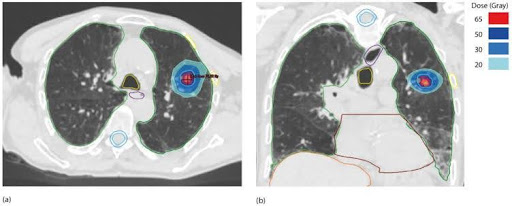

Figure 2: This figure shows an example of the application of SBRT in metastatic lung cancer: dosimetry of a 55 Gy lung SBRT in five fractions of 11 Gy each for lung metastases of primary lung cancer. (a) Axial view, (b) coronal view. The gross tumour volume (GTV) is shown in red, the planning target volume (PTV) in blue and the marker points in green.2